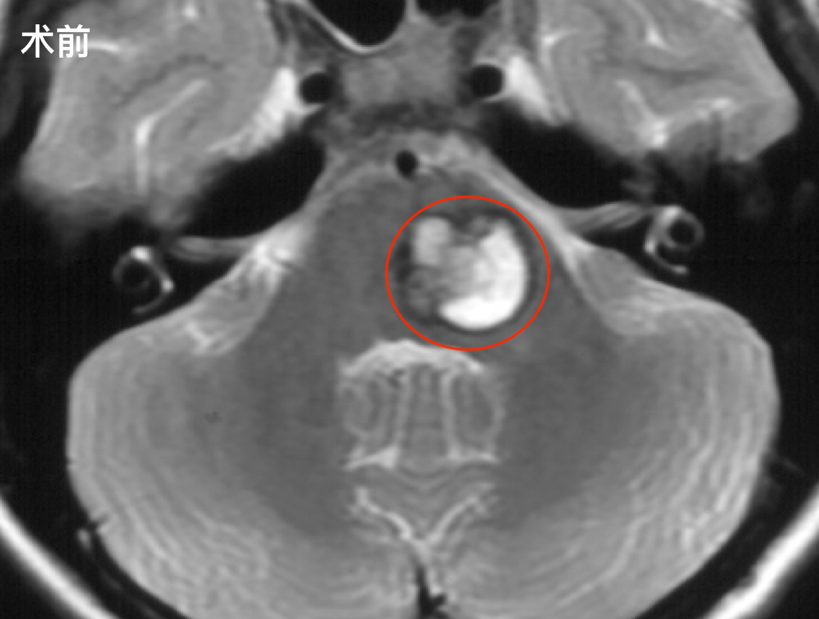

毫无任何预兆,她突然感觉左侧肢体出现无力,左脚发软、抬不起来,正常走路都变得举步维艰。家人立即将她紧急送医,颅脑核磁共振检查的结果让所有人的心瞬间沉了下去——脑干桥脑海绵状...

脑干脑桥海绵状血管瘤是导致这类出血事件的常见病因之一。这类病变具有反复出血的特性,每一次发作都可能在脑干留下不可逆的损伤痕迹,多次出血累积后果极为严峻。...